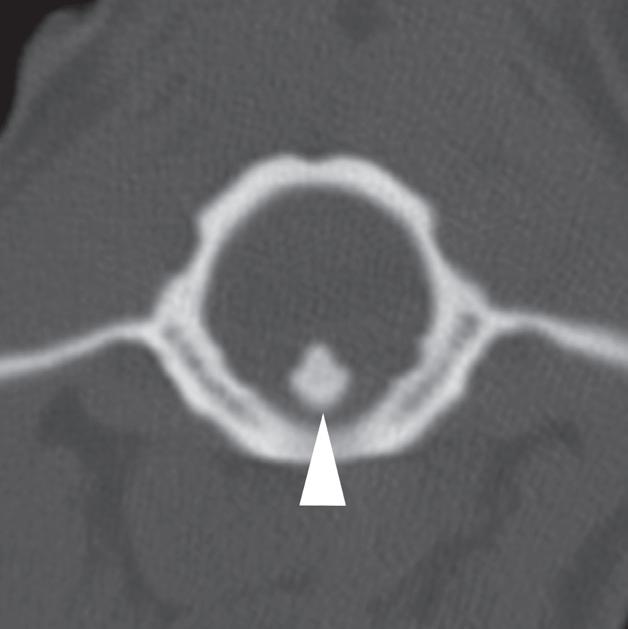

Badanie wykonano u 2-letniej samicy owczarka australijskiego z bólem odcinka szyjnego kręgosłupa, ale bez deficytów neurologicznych, która 9 dni przed badaniem wpadła na ogrodzenie. Obrazy przedstawione na ryc. a–c ułożono od strony czaszkowej do ogonowej na poziomie zęba obrotnika (a – grot strzałki), doczaszkowej części C2 oraz środkowej części trzonu C2. Obraz na ryc. d to rekonstrukcja w płaszczyźnie strzałkowej przez linię pośrodkową, a na ryc. e zamieszczono obraz wykonany w pobliżu płaszczyzny strzałkowej obejmujący ząb obrotnika (e – grot strzałki). Widać przemieszczenie skośnego złamania trzonu kręgu obrotowego (axis) (b–f – strzałka). Przemieszczenie fragmentu złamania względem atlasu powoduje znaczne zmniejszenie średnicy kanału kręgowego (b – gwiazdka). Złamanie jest widoczne na radiogramie (g – grot strzałki), jednak poziomu zwężenia kanału kręgowego nie da się ocenić równie dokładnie jak na obrazach TK. Ze względu na upływ czasu od urazu i brak objawów neurologicznych pacjentkę leczono zachowawczo, jednak właściciel zwierzęcia nie zgłosił się na dalsze wizyty kontrolne